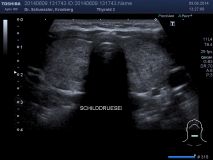

Farbkodierte Ultraschalluntersuchung der Schilddrüse

Die Ultraschalluntersuchung der Schilddrüse ist das Standardverfahren zur Beurteilung der Schilddrüse. Sie ist einfach durchzuführen und für den Patienten nicht belastend.

Mit dieser Untersuchung lassen sich die Schilddrüsengröße, ihre Struktur und auch Knoten, Zysten oder entzündliche Veränderungen sichtbar machen. Durch Hinzunahme der Farbkodierung lässt sich auch die Durchblutungssituation der Schilddrüse sichtbar machen.